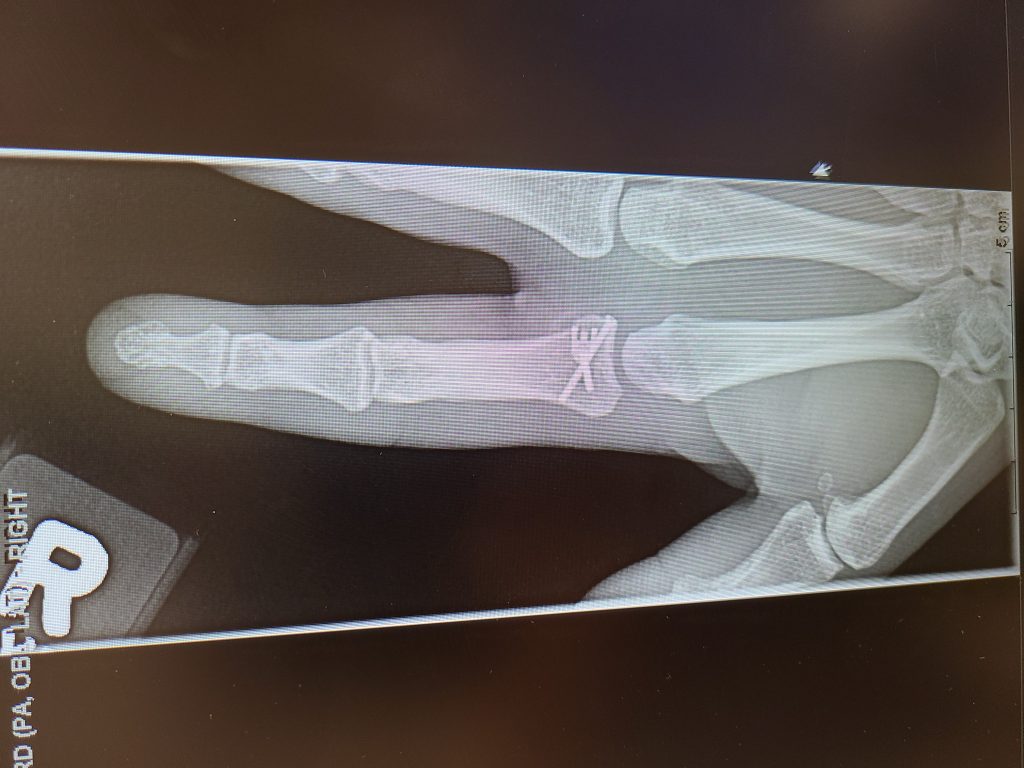

My story begins when my finger was broken one night in April. Wow, that was painful! I then went to the ER and after a couple of x-rays, they confirmed my finger was actually broken. The next phase was to find the best doctor to help fix my broken finger. I had previously been to HSS for my knee and thought there is nowhere else I would go other than HSS. I went through the HSS directory and after a few phone calls to inquire I zeroed in to meet with Dr. Save. I was very impressed with his experience and even more impressed when I met him. I told Dr. Save that I am an avid firearms shooter and that I've been shooting for over 20 years. I take part in shooting competitions all throughout the year and THE most important part of my body is my trigger finger! Dr. Save said that he has a plan to help me get back on track, and I had full confidence that he will. After I woke up from the surgery, he said that it went very well and that we need to start on the road to recovery. I met with Dr. Save all throughout the healing process and each time we met, he was impressed with how well the surgery went and how my finger was healing. Today, I am Back in the Game! I'm at the range every weekend and enjoying every minute of it. My finger is back to normal, I have full range of motion, no pain whatsoever and more importantly my quality of life is back to normal as well. I have 3 small children at home and the day to day of being a dad, a husband, a homeowner and an avid marksman, everything came back to the way it was. I wanted to share my story to let everyone know how thankful I am for Dr. Save and thankful he helped me get back to the things I love the most in life with his incredible gift and talent as a surgeon. Thank you, Dr. Save, you SAVED me! And of course, Thank you HSS!